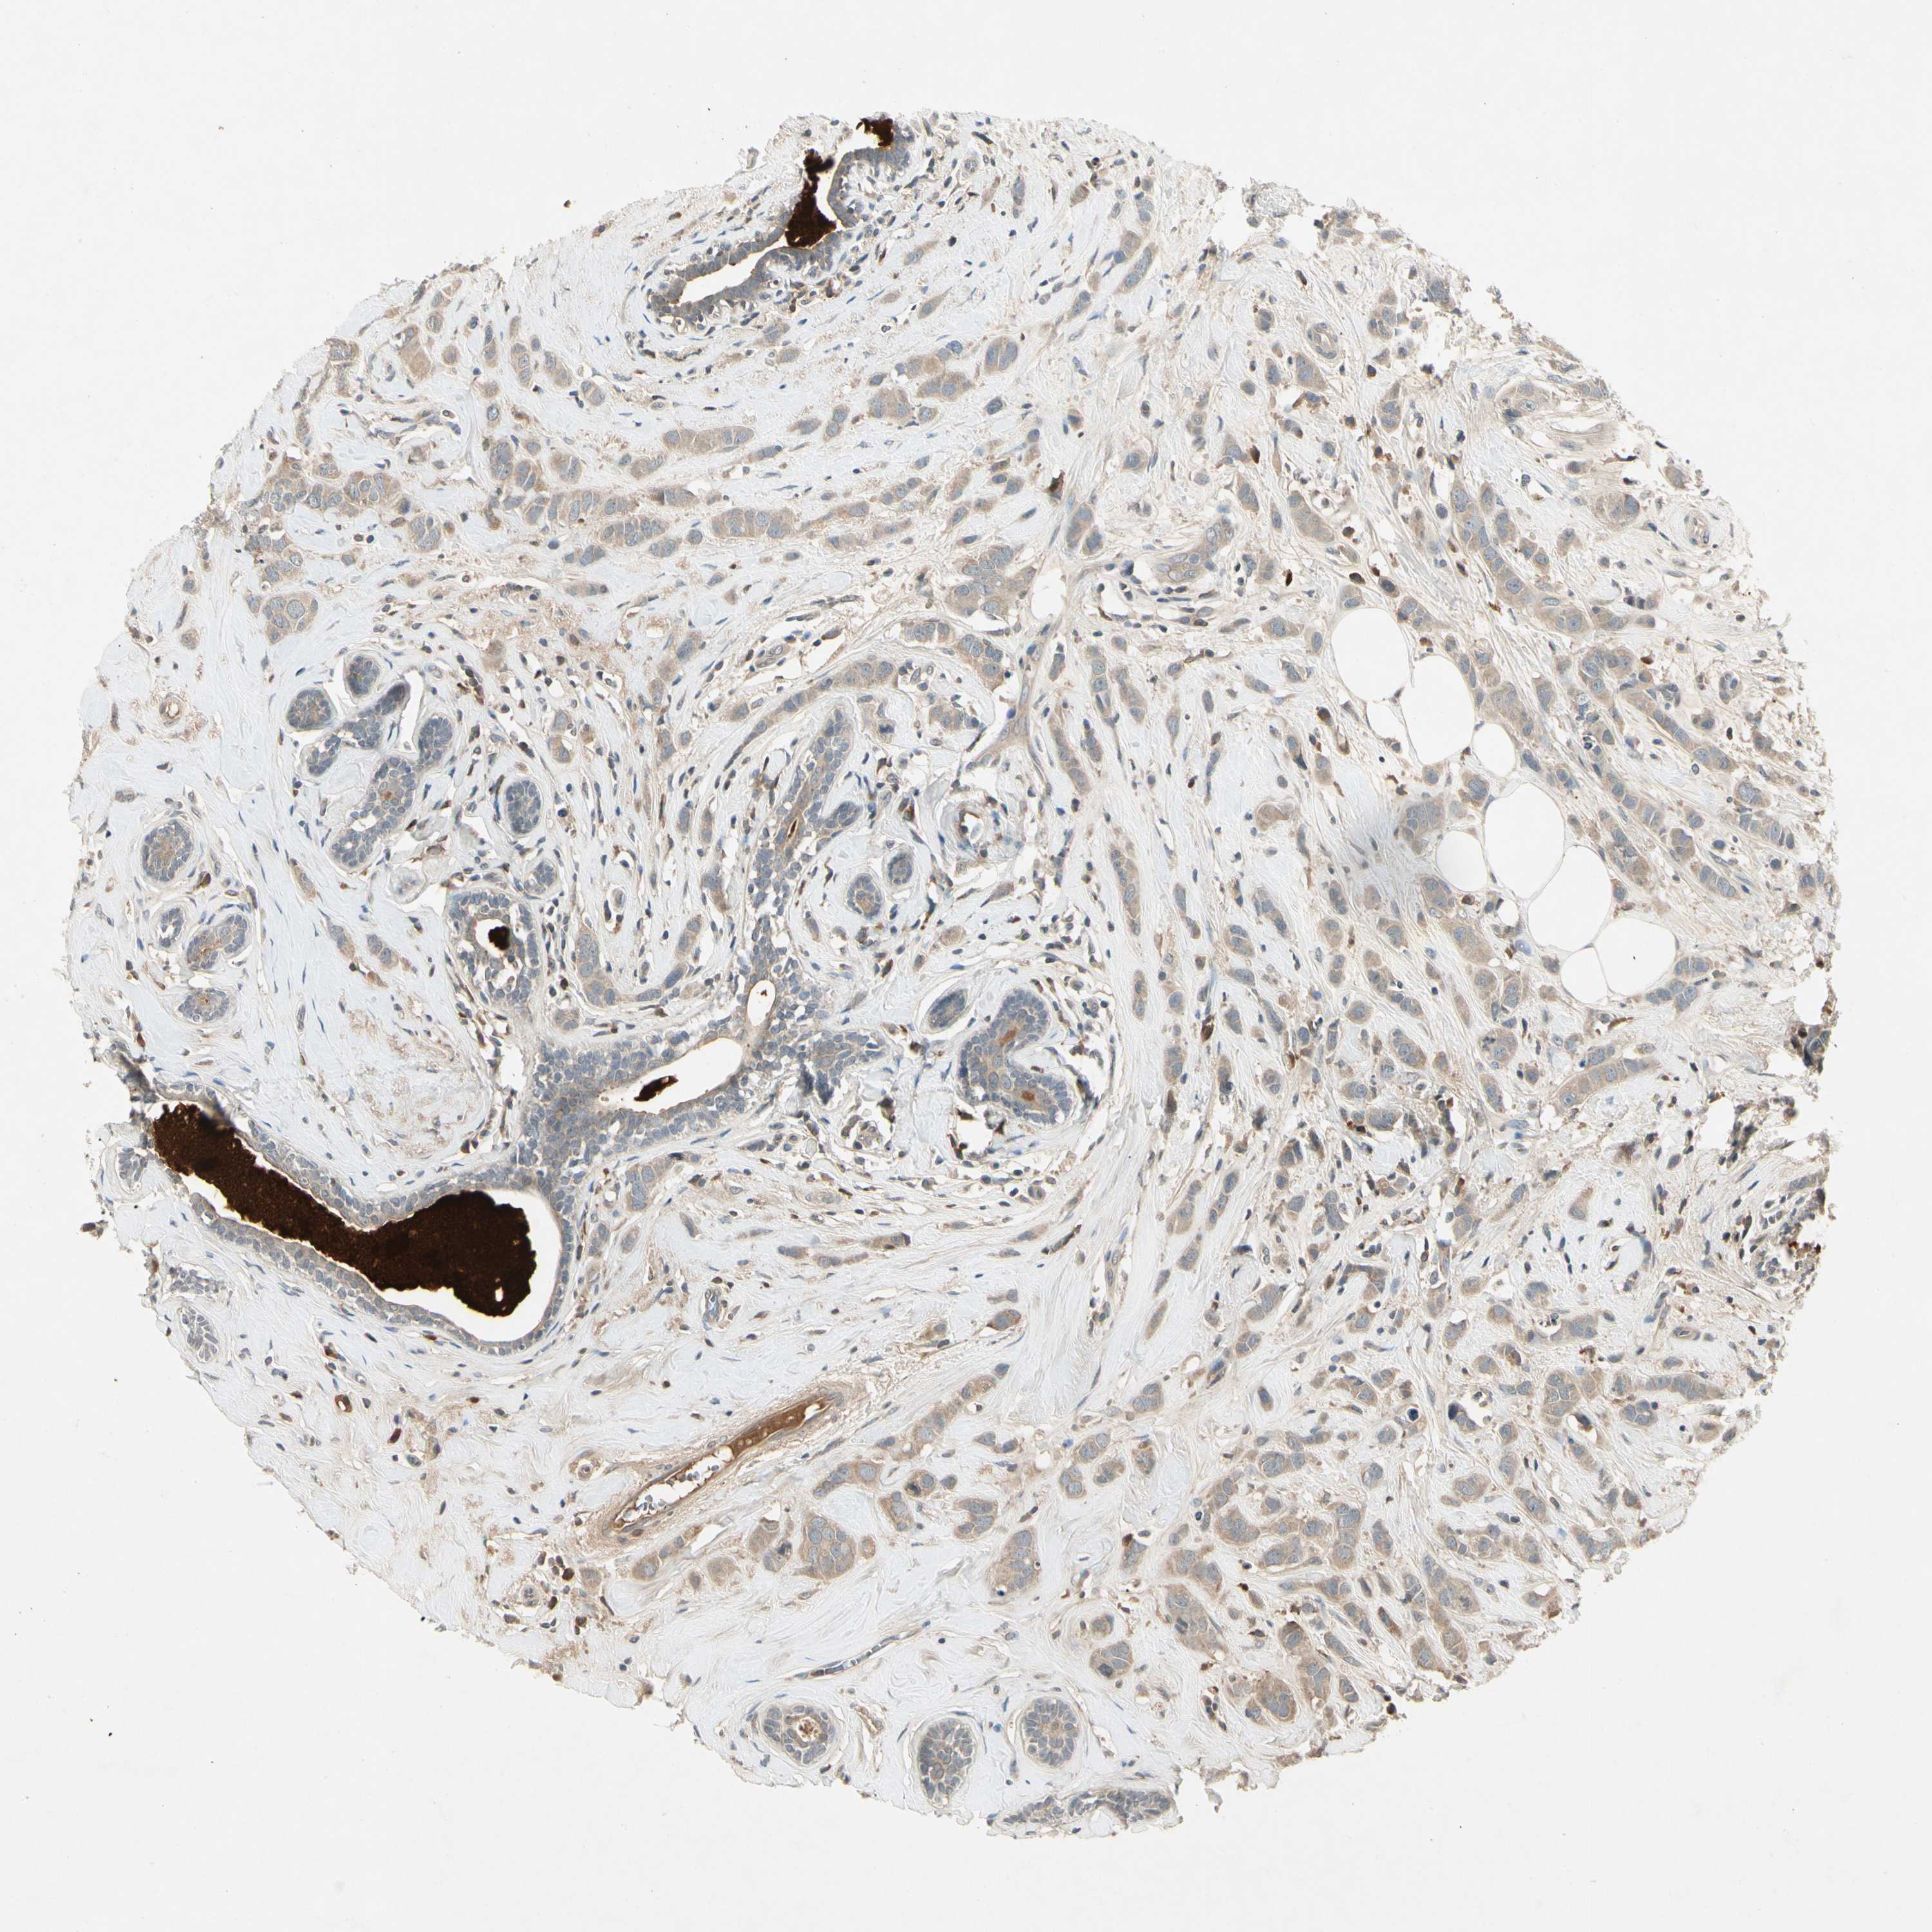

CCL4

CANCER BREAST CANCER Show tissue menu

BRCA TCGA BRCA VALIDATION PROTEIN EXPRESSION

Breast cancer

Human cancer